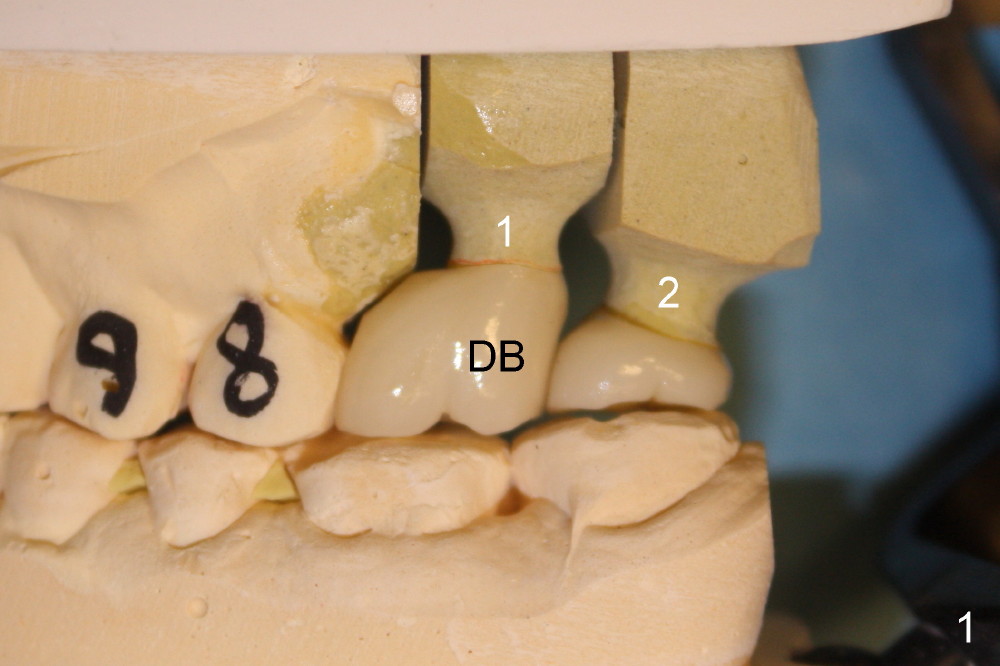

On the day of delivery, the model is studied (Fig.1 (buccal), 2 (lingual), 3 (occlusal)). The implant at the site of the1st molar (#1 in Fig.1-3) is placed distally; it is at the distobuccal cusp (DB in Fig.1). The crown of the 2nd molar (#2) has to extend mesially (Fig.2 arrow) for compensation. The buccolingual width of these two upper molar crowns is reduced, as evidenced by the edge to edge or mild cross bite of occlusal scheme (Fig.4). Anyway, it appears that the implant at the first molar is malpositioned. How to prevent it?